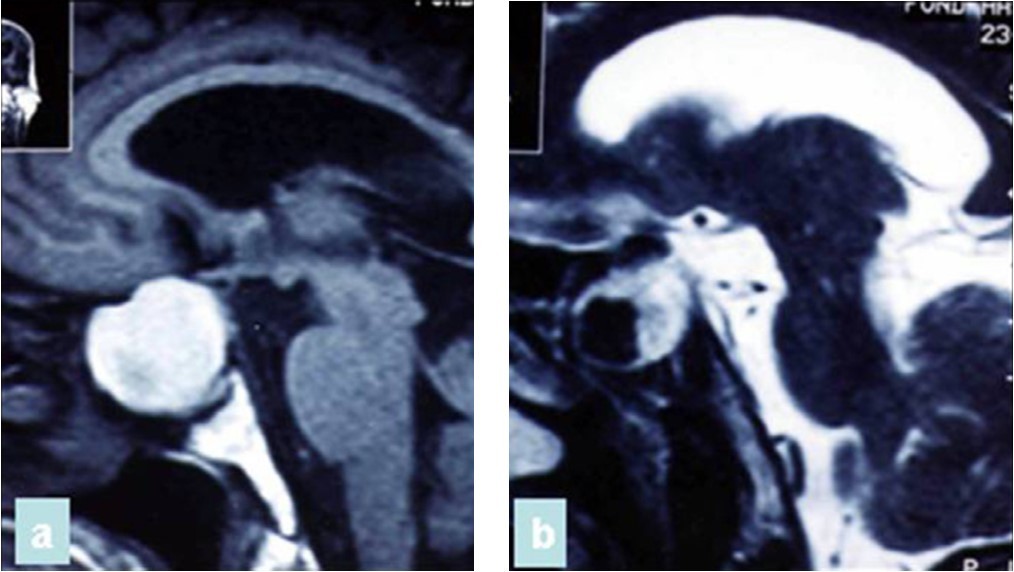

A 47 year old patient with no previous medical history presented with features of raised intracranial pressure, statokinetic cerebellar syndrome as well as left sided hemiparesis. The diagnosis of posterior fossa space occupying lesion was made. Neuroradiologic investigations demonstrated posterior fossa lesions. Magnetic resonance imaging and spectroscopy were in favor of a multiple infective process (Figure 1). Stereotatic biopsy was carried out on the patient and parasitological and histological examinations of the specimen concluded to a filamentous fungal infection of Aspergillus type. Culture and staining techniques categorized the specie as Aspergillus fumigatus (Figure 2).

Figure 1.cerebral MRI axial T1-weighted (A) and coronale (B), showing a multiples well circumscribed posterior fossa lesions

A 65 year-old man presented with progressive visual decrease and ptosis in the left eye. Neurological examination revealed paresis of the 3rd left cranial nerve. Fundoscopy revealed bilateral papillary paleness and visual acuity was: 4/10 at left; 7/10 at right. No signs of endocrine insufficiency or hypersecretion were assessed. There was no evidence of sinusitis. Chest X-ray, routine laboratory investigations and hormonal blood tests were normal. A CT scan showed a hypodense mass enlarging the sphenoid sinus and sellar region with calcification like images and bone erosion of the sellar floor (Figure 5). MRI showed a mass of 26 mm x 33 mm x 25 mm in the sphenoidal sinus ans sellar region, with hypersignal intensity in T1-weighted (Figure 6A) ans T2-weighted sequences, and hyposignal zone in T2-weighted sequences (Figure 6B). Imaging investigations were suggestive of unusual pituitary macroadenoma. The patient underwent a transnasal transsphenoidal approach for excision of the mass. A yellow-brownish gluey material with gummy debris was aspirated from the sphenoid sinus, which was completely cleaned. The sellar floor was eroded which allowed a view of the intact inflammatory dura. An intra-operative presumptive diagnosis was made of caseating granuloma (i.e tuberculosis). The post-operative course was uneventful: the patient recovered from ptosis and visual acuity improve at discharge. Mycobacterium tuberculosis could not be cultured from specimens; and cultures on Sabouraud’s medium did not isolate Aspergillus. Pathologic findings were of non invasive aspergillosis, with many septated fungal hyphae being present without tissue invasion. The patient was not given antifungal drugs because the intrasphenoidal material was completely aspirated. At 6 month and 18 months follow up, the patient had no neurological complaint. No recurrence was observed on control CT scans.

Figure 5.CT scan showing a hypodense mass enlarging the sphenoid sinus and sellar region with calcification like images and bone erosion of the sellar floor

Figure 6.(a) Sagittal T1-weighted MRI showing a well circumscribed hyperintense process in the sphenoidal sinus and sellar region; (b) parasagittal T2-weighted MRI showing a regular hypointense zone into the hyperintense process which is specific to aspergillus infection and corresponds to iron accumulation